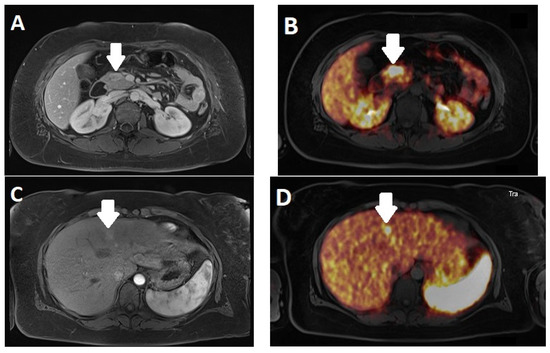

- Beiderwellen, K.J.; Poeppel, T.D.; Hartung-Knemeyer, V.; Buchbender, C.; Kuehl, H.; Bockisch, A.; Lauenstein, T.C. Simultaneous 68Ga-DOTATOC PET/MRI in patients with gastroenteropancreatic neuroendocrine tumors: Initial results. Investig. Radiol. 2013, 48, 273–279. [Google Scholar] [CrossRef]

- Sawicki, L.M.; Deuschl, C.; Beiderwellen, K.; Ruhlmann, V.; Poeppel, T.D.; Heusch, P.; Lahner, H.; Fuhrer, D.; Bockisch, A.; Herrmann, K.; et al. Evaluation of (68)Ga-DOTATOC PET/MRI for whole-body staging of neuroendocrine tumours in comparison with (68)Ga-DOTATOC PET/CT. Eur. Radiol. 2017, 27, 4091–4099. [Google Scholar] [CrossRef]

- Rajamohan, N.; Khasawneh, H.; Singh, A.; Suman, G.; Johnson, G.B.; Majumder, S.; Halfdanarson, T.R.; Goenka, A.H. PET/CT and PET/MRI in neuroendocrine neoplasms. Abdom. Radiol. 2022, 47, 4058–4072. [Google Scholar] [CrossRef] [PubMed]

- Gao, J.; Xu, S.; Ju, H.; Pan, Y.; Zhang, Y. The potential application of MR-derived ADCmin values from (68)Ga-DOTATATE and (18)F-FDG dual tracer PET/MR as replacements for FDG PET in assessment of grade and stage of pancreatic neuroendocrine tumors. EJNMMI Res. 2023, 13, 10. [Google Scholar] [CrossRef] [PubMed]

- Weber, M.; Kessler, L.; Schaarschmidt, B.; Fendler, W.P.; Lahner, H.; Antoch, G.; Umutlu, L.; Herrmann, K.; Rischpler, C. Treatment-related changes in neuroendocrine tumors as assessed by textural features derived from (68)Ga-DOTATOC PET/MRI with simultaneous acquisition of apparent diffusion coefficient. BMC Cancer 2020, 20, 326. [Google Scholar] [CrossRef]